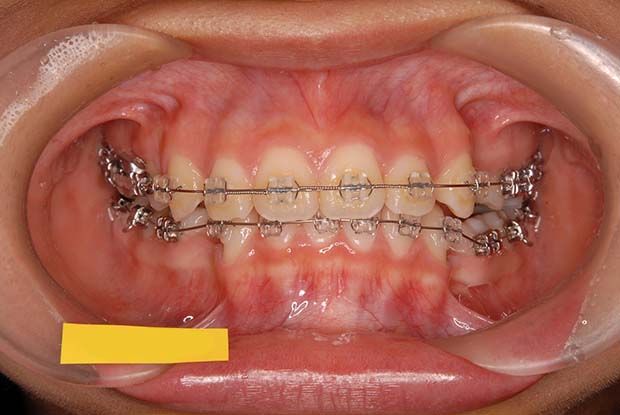

【叢生】抜歯 表側マルチブラケット装置

| 主訴 |

ガタガタ、上の歯が裏側に入っている |

||

|---|---|---|---|

| 診断名 |

左側側切歯crossbiteを伴うAngle I級上下顎前突 |

||

| 年齢 | 21歳 | 性別 | 女性 |

| 治療に用 いた装置 |

唇側マルチブラケット装置 (メタルワイヤー) | 抜歯部位 | 上下顎両側第一小臼歯 |

| 治療期間 ・回数 |

2年6か月・30回 | 治療費 概算 |

約75万円 (調整料を含む) |

| 治療内容 詳細 |

表側のマルチブラケット装置で治療した典型的な抜歯症例です。抜歯したスペースを利用して前歯を後退させ、ガタガタを解いています。 |

||

| リスク・ 副作用 |

装置による違和感。疼痛など |

||